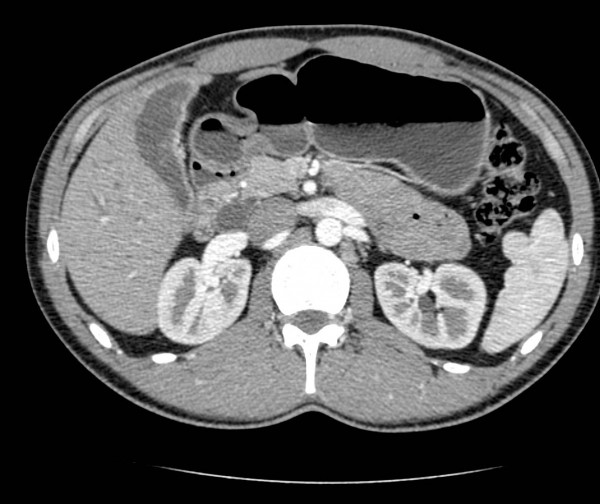

Компьютерная томография (КТ) желчного пузыря